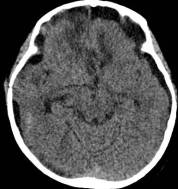

病例1:患儿男性,9岁。因反复出现意识丧失、视力降落半年收入院。入院后CT及 MRI显示颅内有形态不规则、“超大型”的颅咽管瘤,最大径约10厘米,见图1、图2。

鉴于肿瘤体积超大,而且患儿间断出现意识障碍,直接作手术完全切除肿瘤的难度很大,为降低手术风险,所以我们采用先穿刺肿瘤囊减少肿瘤体积,降低颅压,二期手术争取完全切除肿瘤的策略。行肿瘤囊肿穿刺后,引流出约100多毫升囊液,肿瘤体积显著变小,见图3、图4。

图2.术前MRI

白色箭头指示肿瘤下极达枕大孔区